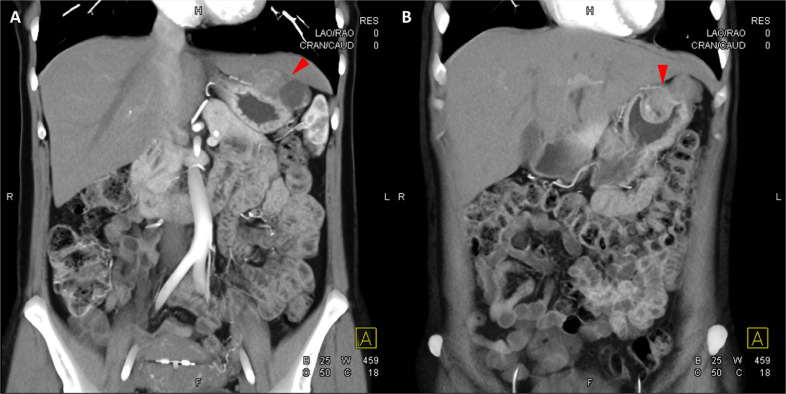

Fig. 4

圖 4: 胃腸道間質瘤的三維表示。 (A 和 B)胃腸道間質瘤在動脈期和冠狀面的 3D 可視化提供了進一步的解剖細節(jié)和空間信息。